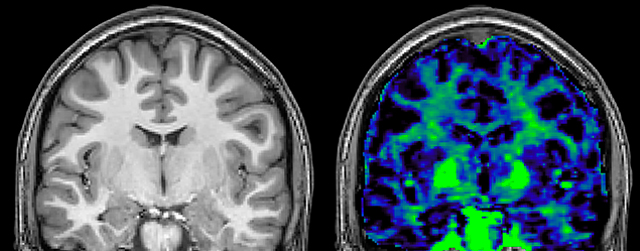

At UBC, a lot of the MS-related work focuses on myelin imaging. “We're born with very little myelin and that increases as the brain grows, which is important for nerve signal propagation. Multiple sclerosis on the other hand, degenerates the myelin with the opposite effect. So, myelin has a really important role in brain function, and having a tool that measures myelin can be extremely useful, we feel,” says Dr. MacKay.

Myelin water imaging (MWI) is a breakthrough technique that was pioneered at UBC for measuring myelin content in the brain, in vivo. “Because the T2 time of water in myelin is much shorter than the T2 of water in the intraand extracellular spaces, we can separate out the myelin water signal.”

The techniques for measuring myelin have changed a lot over the years. “Since we are using the Elition, our myelin water images are much better. We're now acquiring 1 x 2 x 5 mm voxels and displaying at 1 x 1 x 2.5 mm. For a whole brain we can now measure the fraction of water in the myelin component in only about five or six minutes,” Dr. MacKay says.

“We are actually starting to apply this technique in clinical trials,” says Dr. Kolind. “And I’m really hopeful that this is going to give us more clues about the underlying disability progression in MS and move us towards some treatment options for that aspect of the disease.”

Dr. MacKay adds that researchers at UBC are also involved in trials to examine the effects of MS drug treatments on myelination. “In a way, we’re providing a validation of the drug mechanism,” he says. “Some treatments are designed to promote myelination and unpromote demyelination. We can see that some of these drugs are definitely having an effect on myelin water fraction in the cohorts we’ve been studying, and that’s really exciting for us.”

of limiting MWI to the brain, even without the cerebellum, we can now spend about the same amount of time and scan the whole brain and the cervical spinal cord, which is a huge boost for us.” Dr. Rauscher says, “For MWI we perform 3D T2 with 32 or more echoes. This used to take a long time, but with Compressed SENSE we can decrease this to ten minutes for the whole head. Because of the large field of view (FOV) on the readout direction, we even get information from the brainstem, which we previously missed when we were using the GRASE approach. Having the whole head scan is nice because it has spatial resolution, orientation and FOV that are comparable to the standard 3D clinical MS scans, including the FLAIR and 3D T2, and a 3D T1 for brain volume.”

T1 - Weighted, Myelin Water Fraction Superimposed

Images courtesy of Adam Dvorak, Department of Physics and Astronomy, University of British Columbia